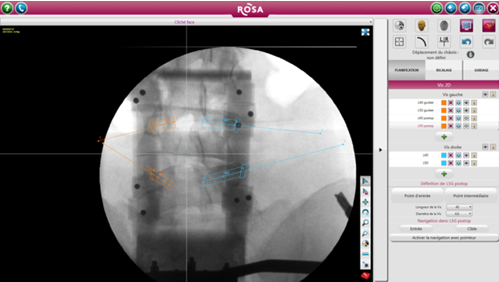

ROSA 是一種影像導(dǎo)航設(shè)備,直接根據(jù)術(shù)中放射線圖像上確定的標(biāo)志或使用導(dǎo)航指針定位工具。引導(dǎo)是基于術(shù)中2D圖像處理軟件完成的軌跡規(guī)劃,隨后患者俯臥位完成注冊(圖1)。在手術(shù)開始時(shí),沿著患者的右手邊放置機(jī)器人,確保機(jī)器人的手臂能充分地覆蓋兩個(gè)節(jié)段(圖2)。然后外科醫(yī)生站在患者的另一邊。手術(shù)室的組織結(jié)構(gòu)圖如圖3所示。

圖1術(shù)前X線透視下椎弓根螺釘?shù)囊?guī)劃